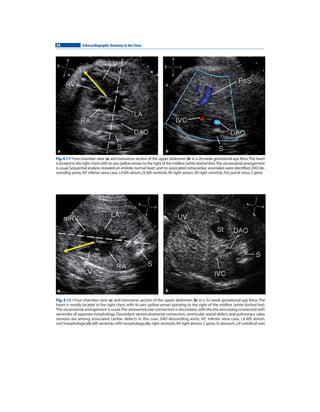

人気のクリスマスアイテムがいっぱい! the in anatomy Echocardiographic fetus PDF | pg 2009 洋書

人気のクリスマスアイテムがいっぱい! the in anatomy Echocardiographic fetus PDF | pg 2009 洋書

Echocardiographic anatomy in the fetus 2009 pg | PDF,

Echocardiographic anatomy in the fetus 2009 pg | PDF, Echocardiographic anatomy in the fetus 2009 pg | PDF,

Echocardiographic anatomy in the fetus 2009 pg | PDF, Short-axis views of a fetus at 22 weeks with double aortic arch and | Download Scientific Diagram,

Short-axis views of a fetus at 22 weeks with double aortic arch and | Download Scientific Diagram, Amazon.com: Echocardiographic Anatomy in the Fetus eBook : Chiappa, Enrico, Cook, Andrew C., Botta, Gianni, Silverman, Norman H.: Kindle Store,

Amazon.com: Echocardiographic Anatomy in the Fetus eBook : Chiappa, Enrico, Cook, Andrew C., Botta, Gianni, Silverman, Norman H.: Kindle Store, Echocardiographic anatomy in the fetus 2009 pg | PDF